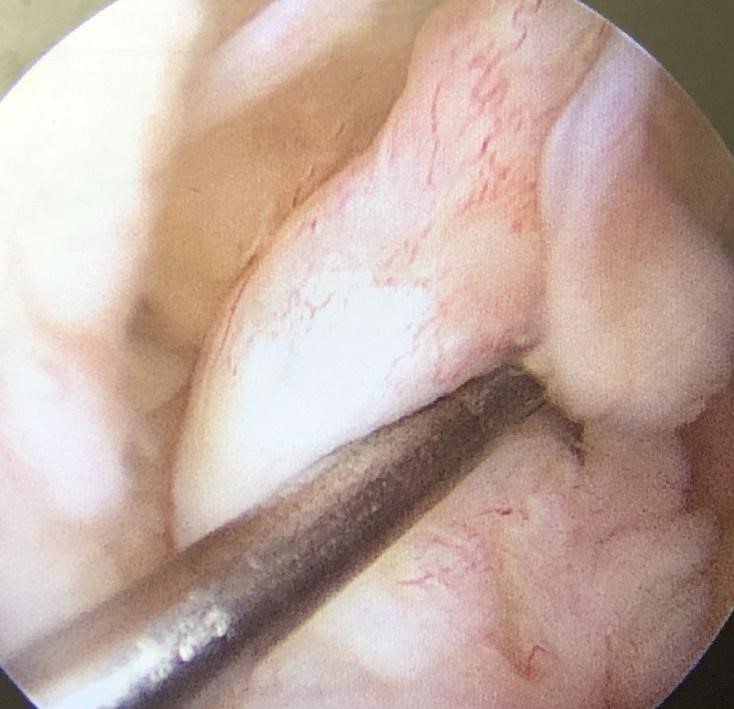

前十字靱帯損傷と半月板損傷を合併している場合には、靱帯再建術と同時に半月板に対しても手術を行います。

手術では、可能な限り半月板を残して縫合する治療を行います。膝関節のクッションの役割をしている半月板がなくなると、関節軟骨に大きな負担がかかってしまい、関節軟骨の劣化が進んでしまうためです。

しかし、損傷の程度によっては半月板を切除しなくてはいけない場合もあります。